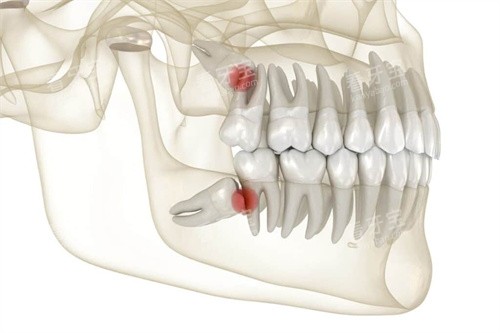

“医生,我这颗牙还有救吗?”

家住北京朝阳的李女士捂着红肿的脸,痛苦地问我。

当我告诉她需要拔除一颗深度阻生的智齿时,她更关心的不是疼痛,而是价格。

3.2 牙齿拔除价格

拔牙价格因牙齿类型和拔牙难度而异:

阻生智齿拔除:500元起

但如果牙齿完全萌出,位置正常,拔除难度相对较小,费用通常在300-500元。

若智齿阻生,特别是低位阻生,价格可能会升至800-1500元。

复杂的阻生智齿拔除,如果需要切开牙龈、去骨等操作,费用可能达到1000-3000元。